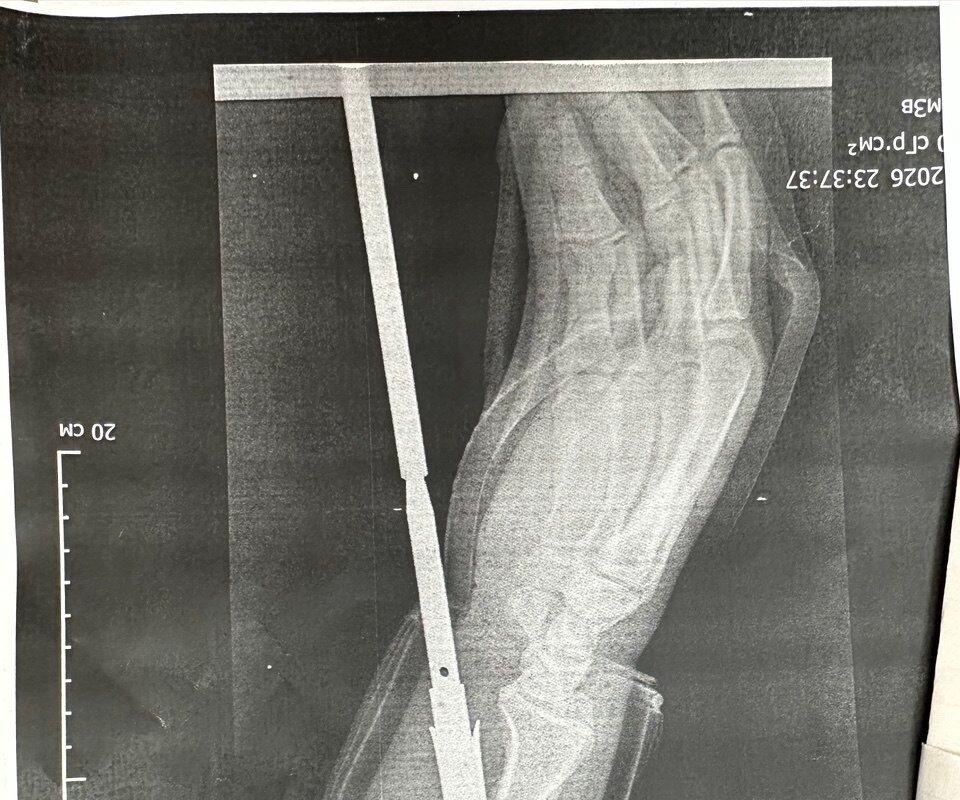

«Гарпун с двумя зубцами прошел между костями, не задев их. Специалисты извлекли инородное тело, обработали колотую рану и оказали пациенту квалифицированную помощь», — говорится в публикации.